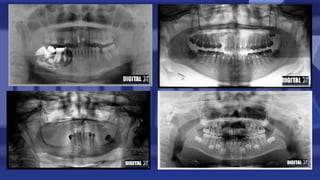

Ofrecemos varios tipos de radiografías digitales, incluyendo panorámicas, cefalométricas y periapicales. Cada paciente recibirá software para que los profesionales puedan ajustar el contraste, nitidez y resolución de las radiografías con el fin de obtener un mejor diagnóstico.